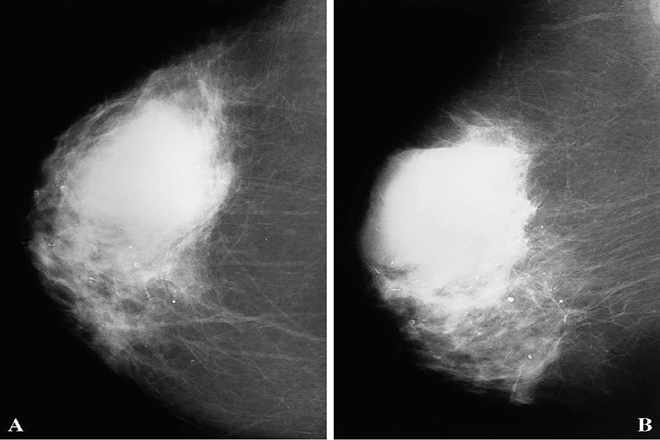

Este estudio fue realizado por radiólogos de la escuela de medicina de las Universidades de Ohio y Northeastem y el artículo publicado en 2010 en la Revista Ultrasonido. El objetivo del presente fue determinar la sensibilidad y especificidad de las imágenes de elasticidad en tiempo real (IE) y el ultrasonido en modo B (US) para la caracterización de las lesiones de mama en benignas ó malignas.

Desde Diciembre de 2003 a Septiembre 2007 se estudiaron 208 pacientes con 251 lesiones que se encontraban agendadas para biopsia de mama guiada por US fueron elegidas para realizar imágenes de elasticidad en tiempo real, lo cual significaba 1 ó 2 minutos adicionales al estudio planeado; los primeros 53 casos fueron realizados con el Sistema Elegra (Siemens) y los restantes 198 con el Sistema Antares (Siemens) utilizando un transductor lineal de 5 a 12 MHz y el software de elasticidad del ultrasonido Siemens.

Se calculó un índice entre la longitud de la lesión medida por el modo B del ultrasonido y la longitud de la lesión en la imagen de elasticidad correspondiente así: IE / Modo B; luego se obtuvieron los resultados histológicos de la biopsia de mama y fueron comparados con el índice IE / Modo B.

La mayoría de las lesiones benignas tuvieron un índice IE / Modo B menor a 1 (0.2 – 1.2) con un promedio de 0.75 ± .23; mientras que las lesiones malignas tuvieron un índica IE / Modo B igual ó superior a 1 (1.0 – 3.1) con un promedio de 1.45 ± 0.41; la sensibilidad fue del 100%, la especificidad del 95%, valor predictivo positivo 84% y valor predictivo negativo 100%.

En conclusión las imágenes de elasticidad en tiempo real para caracterizar las lesiones de mama es una técnica que proveen información diagnóstica valiosa y ayudará al clínico a seleccionar mejor a aquellas pacientes para biopsia de mama, disminuyendo el número de biopsias de mama por condiciones benignas.